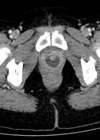

Case 1 A 43-year-old lady presents with urinary incontinence and vaginal pain associated with intercourse. An initial CT scan is performed. Case courtesy of Radswiki, Radiopaedia.org, rID: 12056. Case courtesy of Radswiki, Radiopaedia.org, rID: 12056 What is the clinical diagnosis...